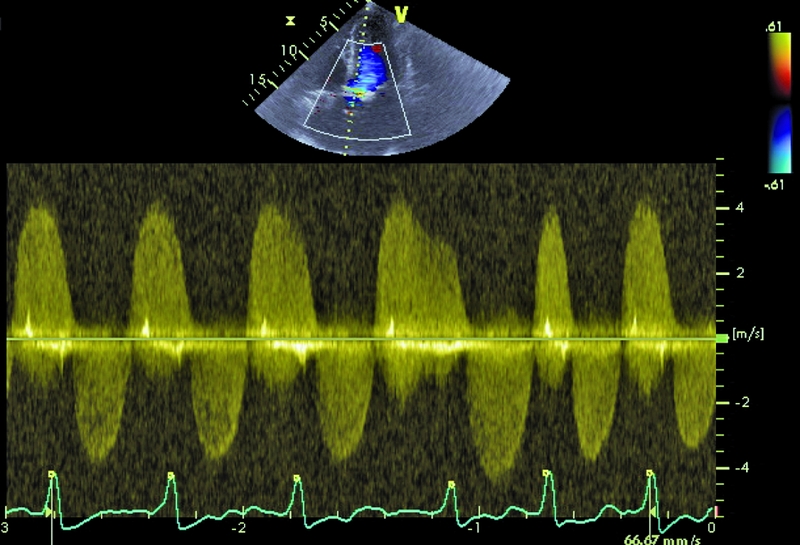

Mężczyzna, lat 79. Jakie patologie można rozpoznać na rycinach?

1. Zwapnienia płatków oraz pierścienia zastawki aortalnej (ryc. 1).

3. Zwężenie i niedomykalność zastawki aortalnej (ryc. 3).